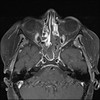

Orbital hemangiopericytoma